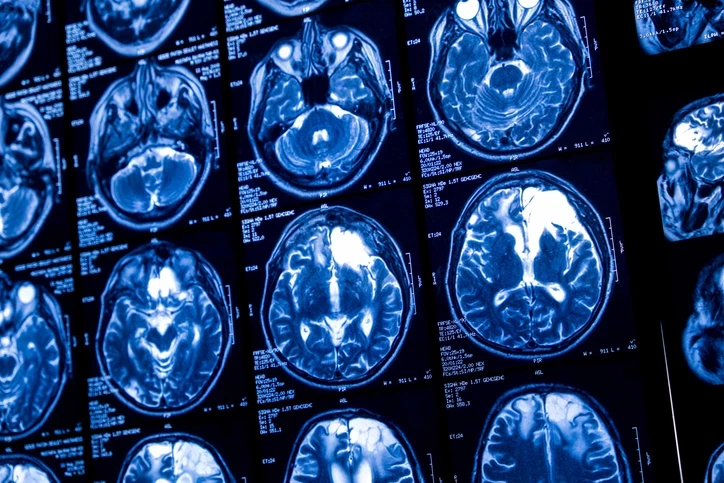

Bilim kurgu filmlerinde yer alan düşünce gücüyle cihaz kontrolü ya da beyne veri aktarımı sahneleri artık yalnızca senaryo olmaktan çıkıyor. 1924 yılında beynin elektriksel aktivitesinin ilk kez Electroencephalography (EEG) ile kaydedilmesinden bu yana nöroteknoloji alanında önemli gelişmeler yaşandı.

Günümüzde beyin sinyallerini okuyabilen ve bazı durumlarda bu sinyalleri düzenleyebilen sistemlerin klinik uygulamalarda kullanılmaya başlandığı belirtiliyor. Uzmanlar, bu teknolojilerin özellikle nörolojik hastalıkların tedavisinde destekleyici yöntemler olarak değerlendirildiğini ifade ediyor.

Vagus Sinir Stimülasyonu (VNS), ilaç tedavisine dirençli epilepsi hastalarında nöbet sıklığını azaltmak amacıyla uygulanan bir yöntem olarak kullanılıyor. Sistem, vagus siniri üzerinden beyne kontrollü elektriksel uyarılar göndererek nörolojik aktivitenin düzenlenmesine yardımcı oluyor. Bazı VNS modellerinin nöbet aktivitesine ilişkin veri kaydı tutabildiği ve bu sayede hastaların nöbet sıklığı ile zamanlamasının daha objektif biçimde takip edilebildiği belirtiliyor.